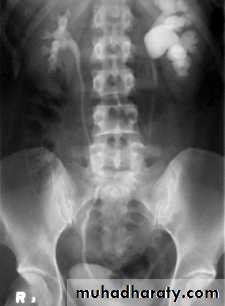

Ectopia vesica :

bladder located at low position & plain x-ray shows separation of symphysis pubis .